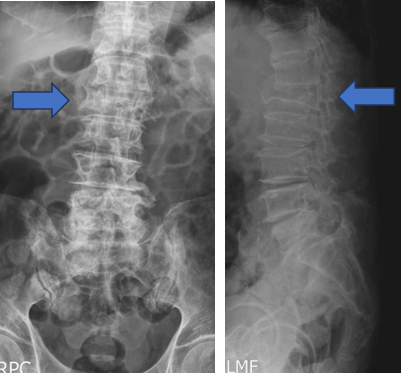

X光:最快速且便利的檢查,可以看到骨頭的構造,對骨折有一定程度的診斷力,但對於較輕微並未造成變形之骨折較難以診斷。除此之外,X光還能檢查是否有其他造成背痛的脊椎退化或骨刺。(圖二)

(圖二)